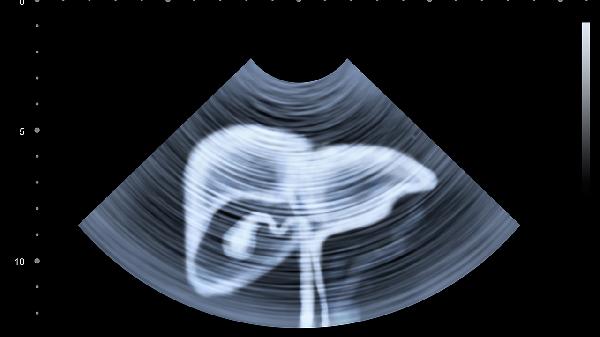

肝脾肿大可致腹部膨隆,叩诊呈浊音。门静脉高压时可能出现腹水,表现为肚脐外凸或腹壁静脉曲张。腹胀常伴有触痛感,婴幼儿会因不适而哭闹不安。